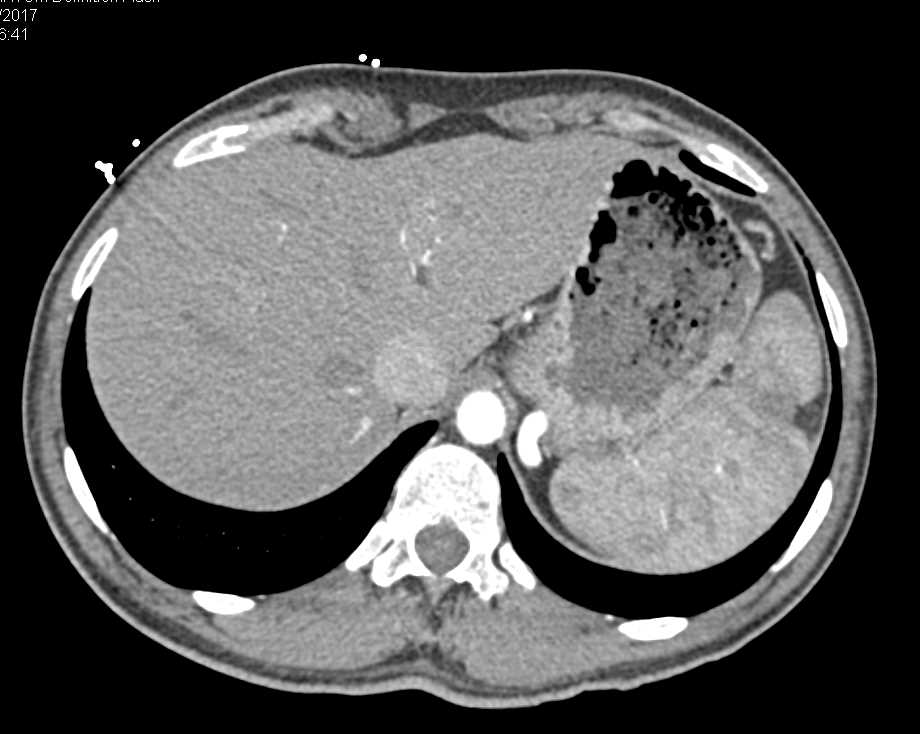

Splenic Infarcts